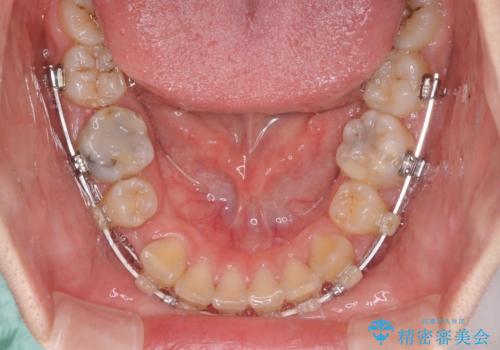

- ハーフリンガル

- 口元の突出感を気にして来院された患者様です。

上下左右の第一小臼歯4本を抜歯して口元を下げる治療計画としました。

目立たない装置が希望であったため、上顎が裏側装置である、ハーフリンガル装置を選択されました。

非常に大きな虫歯のあった下顎大臼歯は、根管治療を行い、矯正治療後にオールセラミッククラウンにて補綴治療を行いました。